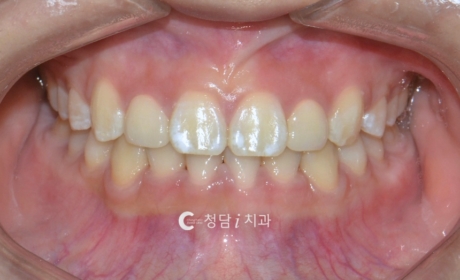

앞니 돌출 및 정중선 틀어짐, 앞니 부분교정 사례

정중선이 어긋나 있고 가운데 앞니가 돌출되면서 옆으로 틀어져 있던 환자분 부분교정 사례입니다. 전체 교정이 아닌 앞니 부분교정으로 진행하여 부담을 줄이면서도 심미적으로 개선할 수 있었는데요.치아 배열이 가지런해지고 돌출된 앞니가 바로잡히면서 훨씬 자연스럽고 조화로운 미소를 찾을 수 있었습니다.